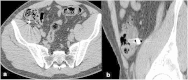

Presentation of cases: First case is a 54-year-old female who accidentally swallowed retractable one-tooth denture during fall about 22 h before admission and clinical manifestation of acute small bowel obstruction developed. The patient underwent laparotomy, enterotomy with retrieval of the foreign body. The second case is a 31-year-old male who accidentally ingested fixed one-tooth prosthesis while eating which impacted in the ileocaecal valve. During the preparation to colonoscopy the denture spontaneously passed out with stools.

Discussion: Denture ingestion is more common among patients with psychoneurologic deficit, alcohol and drug abusers. Among healthy and younger population denture ingestion is rare. Both reported patients are not elder. Thus dislodgement of removable or fixed dentures is another risk factor of denture ingestion. Most common site of denture impaction is esophagus; small bowel impaction is rare. Moreover, in most reported cases, small bowel impaction of ingested dentures leads to small bowel perforation. In our first case the complication of denture ingestion appeared to be bowel obstruction what is even rarer.